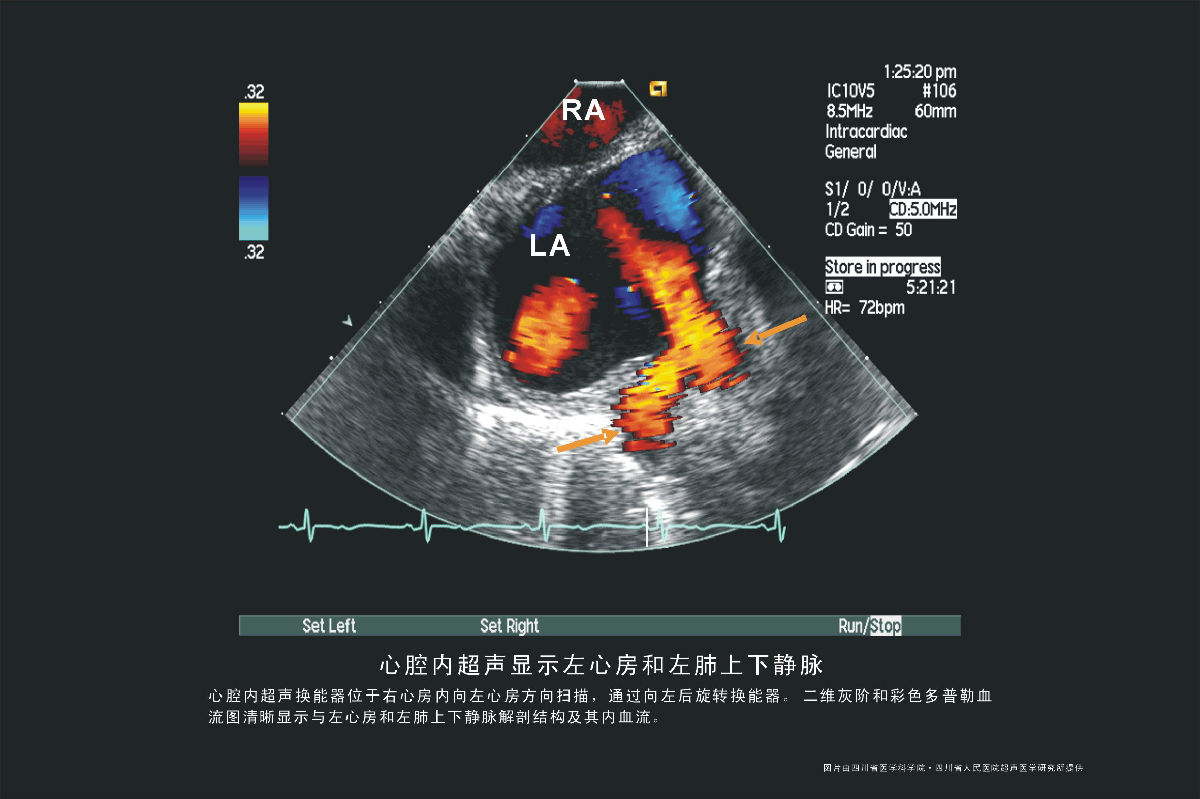

静脉图